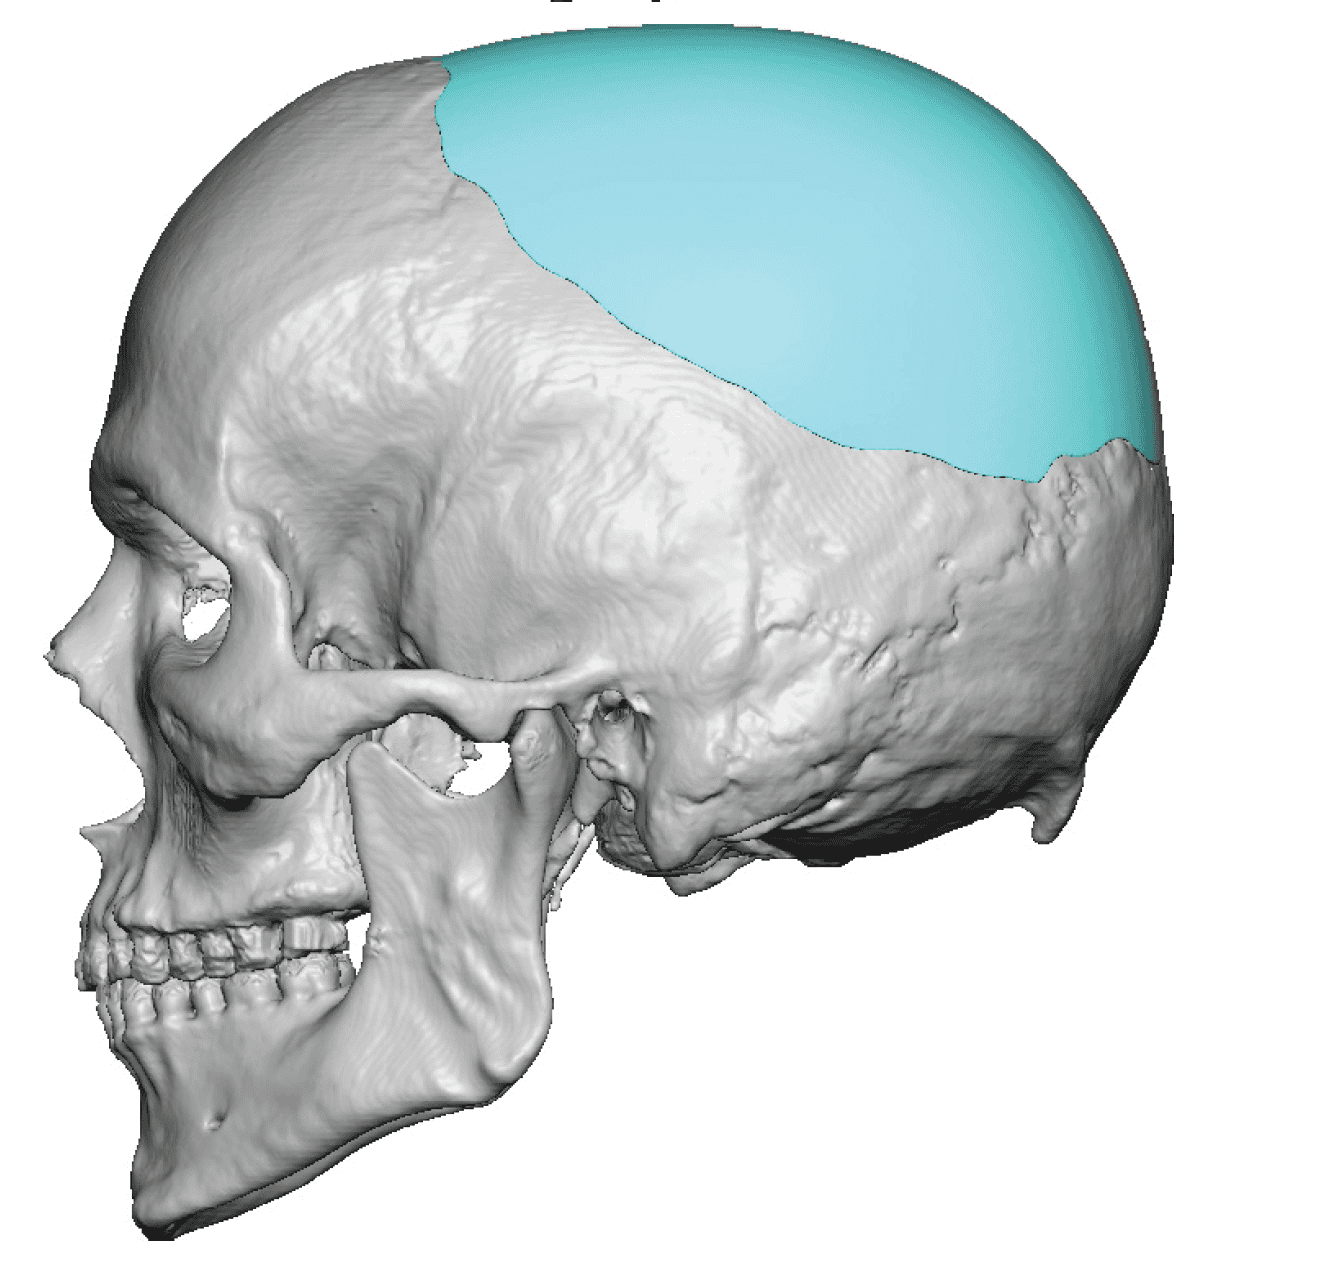

Desire for change of head shape from front view form an inverted V shape to a rounder and wider head shape.

Placement of custom extended forehead-temporal implants through incisions in the crease behind the ear. (he had a prior back of head skull implant which is green in the implant designs and which the head widening implants partially covered it)